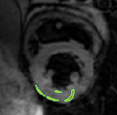

4.2 Visual assessment

We select the case that achieves the highest and lowest dice score for visual assessment. Fig. 4 shows example segmentation results where the proposed method achieved the highest agreement with the ground truth delineations. Fig. 5 shows example segmentation results where the proposed method achieved the lowest agreement with the ground truth delineations.